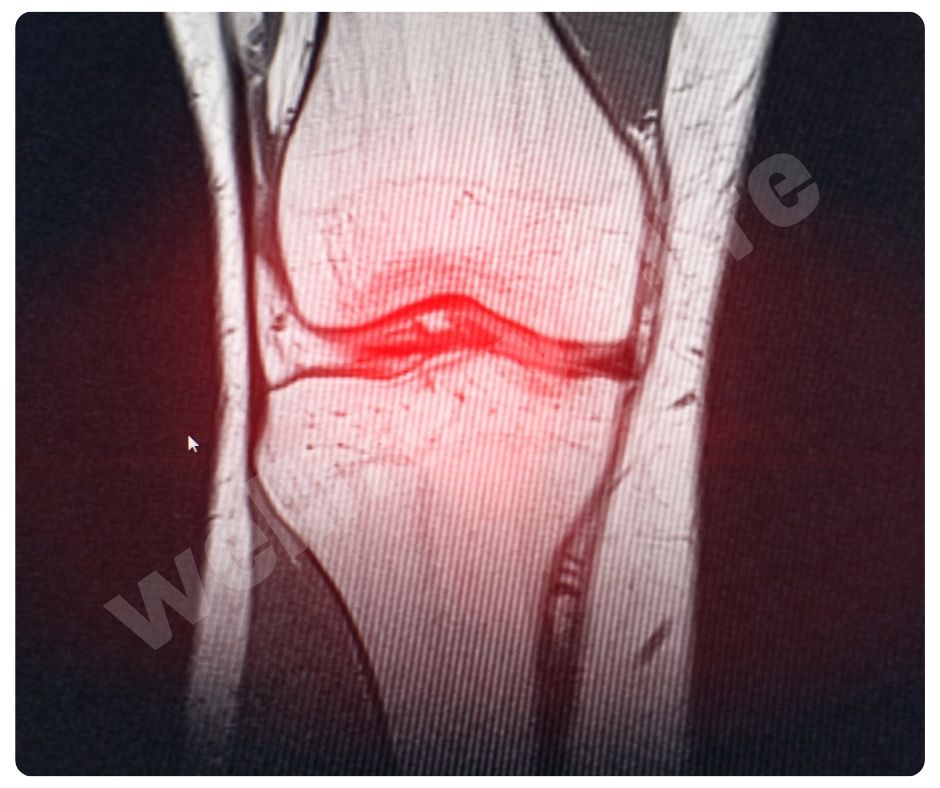

최근 연구에 따르면 글루코사민은 연골 세포의 생성을 촉진하고, 연골 조직의 회복을 돕는 효과가 있습니다. 2023년에 발표된 한 연구에서는 글루코사민이 연골 세포의 대사 활동을 증가시키고, 연골 조직의 손상을 줄이는 데 효과적이라는 결과를 보여주었습니다.

글루코사민의 항염증 효과에 대한 연구도 활발히 진행되고 있습니다. 2022년에 발표된 한 연구에서는 글루코사민이 염증 매개체인 사이토카인의 생성을 억제하여 염증 반응을 줄이는 데 도움이 된다는 결과를 발표했습니다 (UVM College of Medicine). 이는 관절염 환자의 통증과 염증을 효과적으로 줄이는 데 중요한 역할을 합니다.